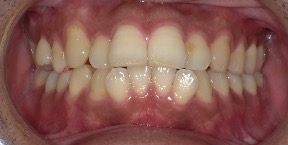

30歳女性のビフォーアフター

| 診断 | 叢生 |

| 治療方針 | 治療方針:インビザラインシステムにて主にIPR(歯と歯の間をわずかに削合してスペースを獲得する方法)を組み込んだ動的矯正治療を行い、叢生を改善後、保定を行う。 |

| 治療費 ※ | 96万5千円(診断、型取り、矯正中のメンテナンス、保定装置を含む料金) |

| 治療期間 | 1年8か月 |

| リスク | 1日20時間以上マウスピースを使用できない場合、歯が動かなかったり、想定しない誤差により不完全に終わる可能性がある。装着時や食事時に痛みを伴う。歯肉退縮や虫歯になるおそれがある。また、指導通りに装着できていない場合や適切なブラッシングが出来ていないとそのリスクが高くなる。歯根が短くなることがある。ごくまれに歯の神経が損傷してしまうことがある。過去にぶつけたり深い虫歯治療をしたことがあるとそのリスクはやや高くなる。矯正後には保定装置が必要。適切な使用ができない場合、後戻りの原因となる。将来的に歯並びが動いて再矯正が必要な場合がある。舌癖(舌で歯を押し出す癖)親知らずが正常に生えていない場合、その可能性がやや高くなる。 |